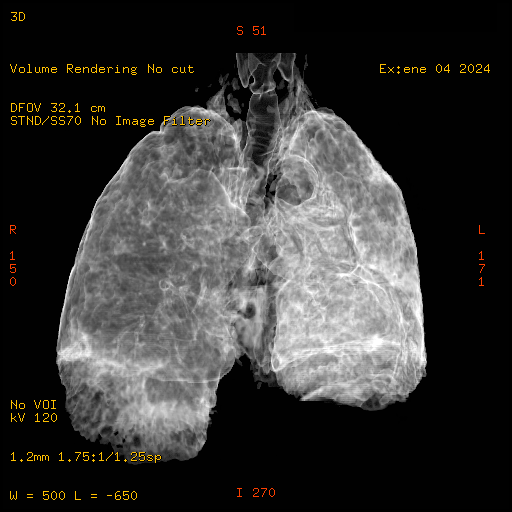

Se coloca al paciente en posición decúbito supino sobre la mesa de tomografía, se le solicita que suba los brazos hacia arriba de la cabeza, se le da las instrucciones para la respiración, se realizan cortes con grosor de 3.75 y un pitch de 1.7, realizando reconstrucciones retrospectivas en diferente plano, diferente grosor utilizando diferentes opciones de software que nos presenta el equipo.

El parénquima pulmonar izquierdo muestra un infiltrado intersticial difuso que causa engrosamiento del septum axial, además del fenómeno de bronquiectasias quísticas se observan pequeñas bulas enfisematosas de localización subpleural que compromete ambas bases pulmonares.

Bronquiectasias cilíndricas, bullas enfisematosas basales bilaterales